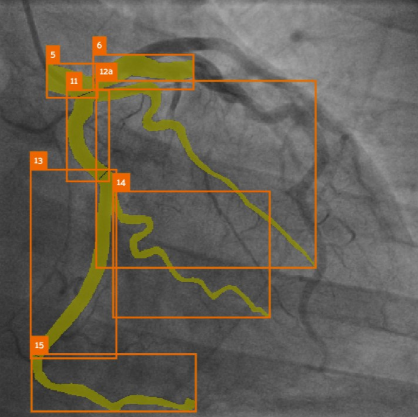

Developed a frame recommendation module based on image quality assessment (integrated into the MPXA product), local refinement module for coronary lesion & bifurcation, video-based complication detection; led MICCAI ARCADE Challenge; automated CFD (PyFluent).

SASS: Semi-Supervised Approach for Stenosis Segmentation (ARCADE Challenge) Lee IK, Shin J, Lee Y-H, Ku JH, Kim H-W β MICCAI Workshop: ARCADE, 2023

MPSeg: Multi-Phase Strategy for Coronary Artery Segmentation (ARCADE Challenge) Ku JH, Lee Y-H, Shin J, Lee IK, Kim H-W β MICCAI Workshop: ARCADE, 2023